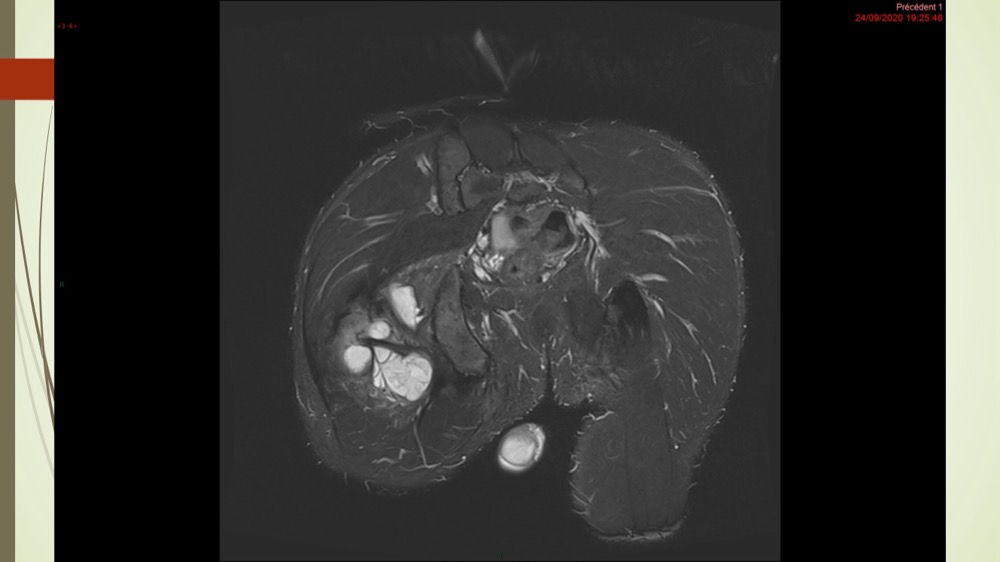

Coxalgie traînante

Kévin Mahé 29/06/2022